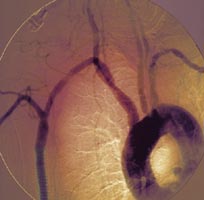

Νέα Υόρκη: Οι καπνίστριες έχουν υψηλότερο του μέσου όρου κίνδυνο εκδήλωσης καρκίνου του τραχήλου της μήτρας, αλλά και οι παθητικές καπνίστριες επίσης κινδυνεύουν να εμφανίσουν κυτταρική βλάβη και έτσι να έχουν ένα μη φυσιολογικό αποτέλεσμα στο τεστ Παπανικολάου, σύμφωνα με νέα αμερικανική έρευνα.